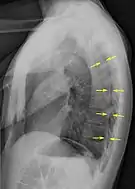

Chest X-ray

A plain chest radiograph, ideally with the X-ray beams being projected from the back (posteroanterior, or "PA"), and during maximal inspiration (holding one's breath), is the most appropriate first investigation.[30] It is not believed that routinely taking images during expiration would confer any benefit.[31] Still, they may be useful in the detection of a pneumothorax when clinical suspicion is high but yet an inspiratory radiograph appears normal.[32] Also, if the PA X-ray does not show a pneumothorax but there is a strong suspicion of one, lateral X-rays (with beams projecting from the side) may be performed, but this is not routine practice.[15][19]

Anteroposterior inspired X-ray, showing subtle left-sided pneumothorax caused by port insertion

Lateral inspired X-ray at the same time, more clearly showing the pneumothorax posteriorly in this case

Anteroposterior expired X-ray at the same time, more clearly showing the pneumothorax in this case